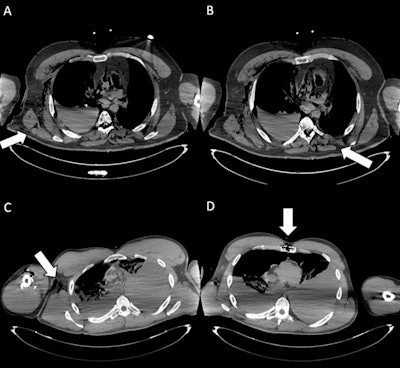

Entry wounds. (A) Axial CT scan shows an entrance wound in the right posterior thoracic wall (white arrow), with adjacent soft-tissue disruption and subcutaneous gas, consistent with a penetrating gunshot injury. (B) Axial CT image depicts the ballistic trajectory with paravertebral left soft-tissue damage (white arrow) and subcutaneous emphysema in the posterior right chest wall. (C) Cross-sectional CT slice demonstrates an entrance wound at the root of the right arm (white arrow), associated with soft-tissue laceration and subcutaneous emphysema. (D) CT image illustrates an entrance wound at the sternal level (white arrow), with anterior chest wall disruption and surrounding soft-tissue alterations, compatible with penetrating trauma. The identification of entrance gunshot wounds showed only moderate inter-reader agreement (Fleiss’ kappa = 0.55). In particular, less forensic-experienced readers demonstrated markedly reduced sensitivity (29.7%), highlighting the diagnostic challenges of detecting these findings on postmortem CT.All figures courtesy of Dr. Maria Grazia Fornasari, Dr. Giuseppe Lo Re, Dr. Roberto Cannella et al and La Radiologia Medica/SIRM.